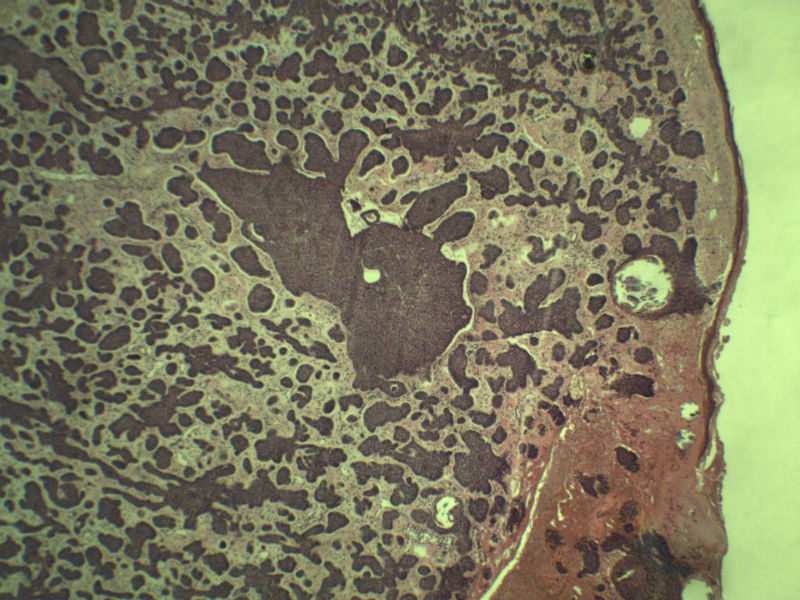

女 67岁 临床考虑面部色素痣 1*0.8 cm  请问各位老师 这是什么? 谢谢!面部包块图1

毛母/发细胞瘤鉴别基底细胞癌,可做CD10,CK7,CK20鉴别

考虑毛发上皮瘤,需除外基底细胞癌。

毛发上皮瘤,需与基底细胞癌鉴别

第一例:毛发上皮瘤

第一例:毛发上皮瘤,与基底细胞瘤区别明显。

第一例  毛发上皮瘤,和基底细胞癌鉴别一下

第一例考虑毛母细胞瘤,第二例考虑基底细胞癌。

第一例:毛母细胞瘤;第二例:基底细胞癌

第一例,毛发上皮瘤;第二例,基底细胞癌。

一毛发上皮瘤